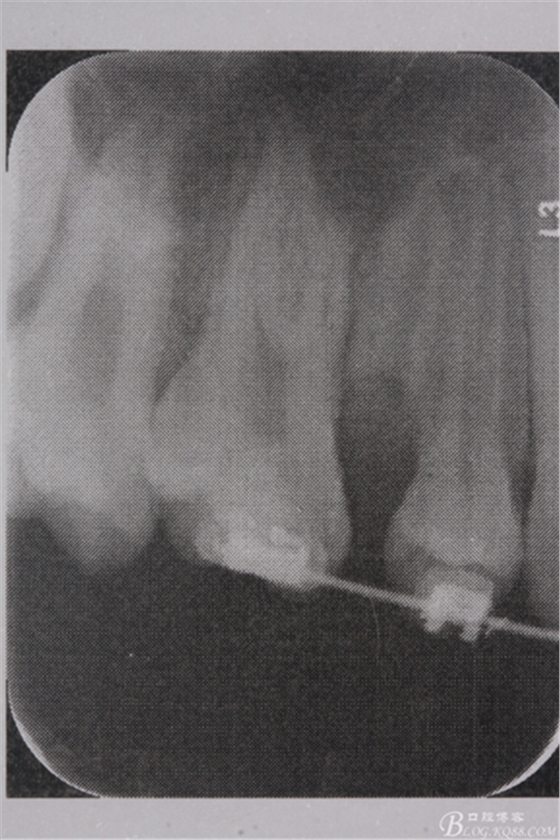

圖4. 加拍局部根尖片,15牙根顯露無疑,遂考慮拔除15,才能關(guān)閉16與14之間的間隙。